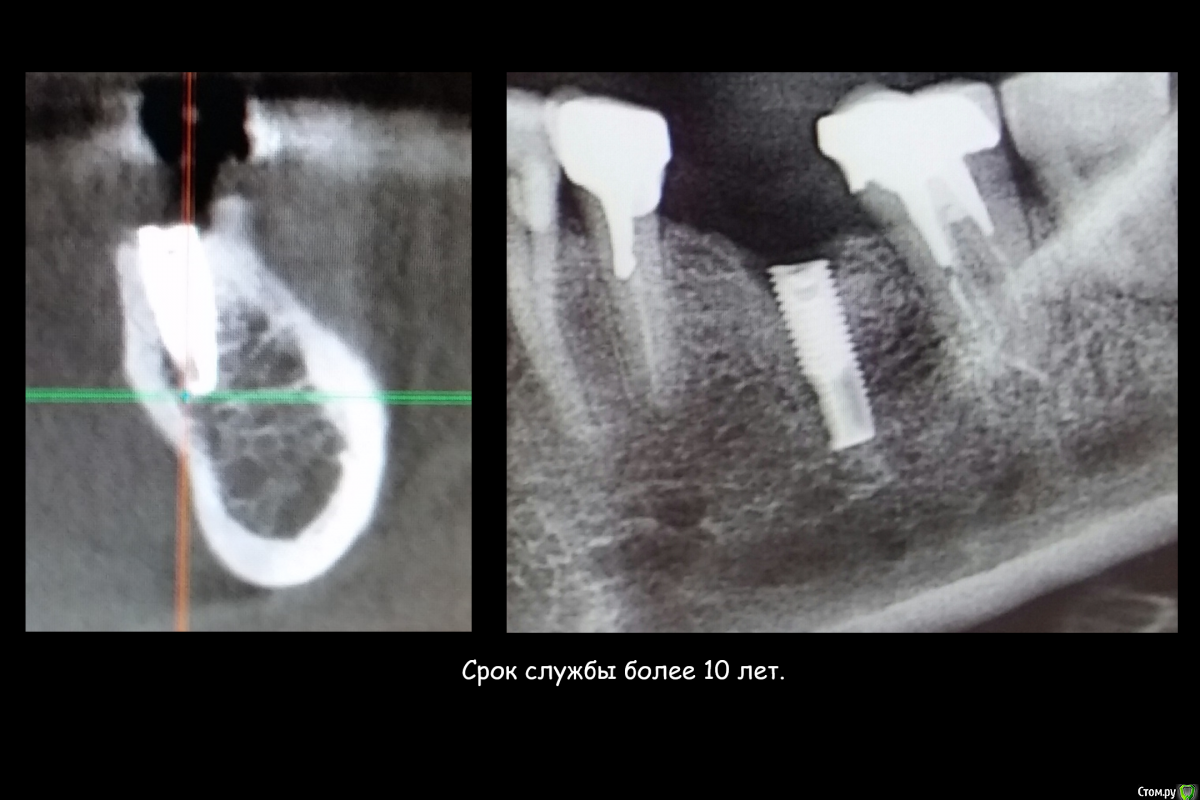

Этот имплантат, можно было лечить!!!!!!